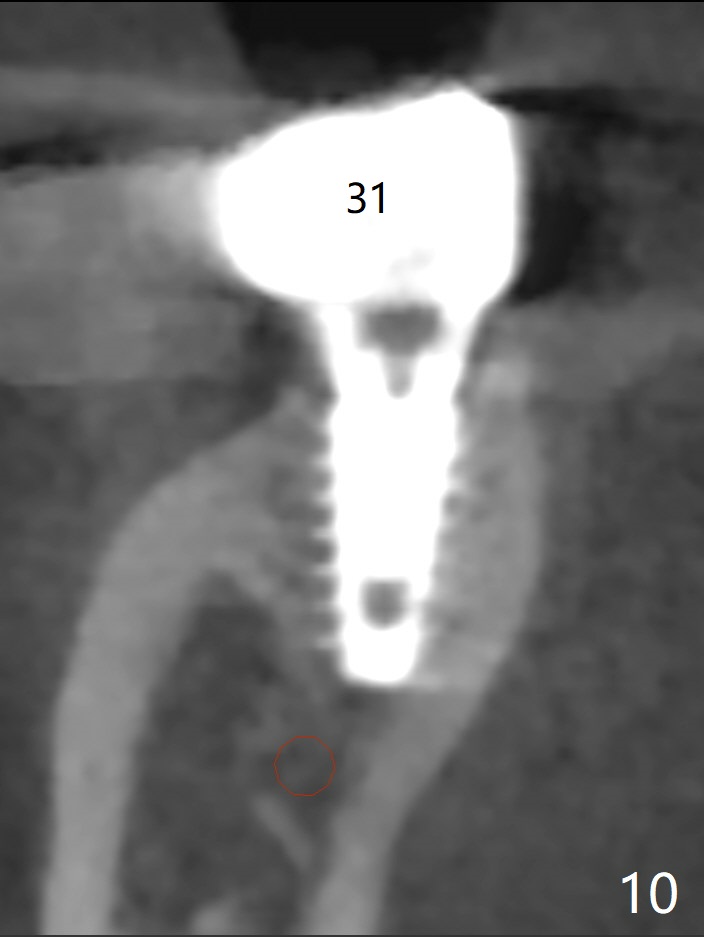

54岁男,右下6,7位点保留后7个月回来植牙,植牙床是个平面(图一),今后两个牙齿之间龈乳头一定缺乏,如何重建?放置导板,稍微使用环形钻头,在6,7植牙床上形成标记(图二),然后切开,植入植体,6扭力低,7高,所以安置愈合(6x5毫米)和修复(5.5x4(4)毫米)基台。原来导板设计把植体植入牙槽嵴(图三:白虚线)下1-2毫米,自动提高植体间牙槽嵴,接着把钻洞产生的骨粉放在后者上缘(*),由近中和远中基台固定。最后覆盖胶原膜,缝合(图四)。原来导板需要切除的角化龈保留住了(图四:7B,7L)。放入修复基台目的是利用它的高度固定牙周敷料。术后3个月7牙槽窝愈合(位点保存后10个月,图五:*),植体间牙槽嵴仍旧高(箭头),6放置修复基台,准备做临时牙冠。右上7反合,需要做局部矫正(图六)。病人非常感激术后三个月制作的临时牙冠(连体)。术后五个月对临时牙冠进行修改:6牙合面垫高(图七:*),这样上下7牙合面分开,上7颊侧放置矫正器,下7牙圈(舌侧有cleat),两者之间安置橡皮筋,上7就可以自由往舌侧移动。术后8.5个月全景片和CT显示植体种植牙槽嵴下(图八至十),这也是重建龈乳头基础。